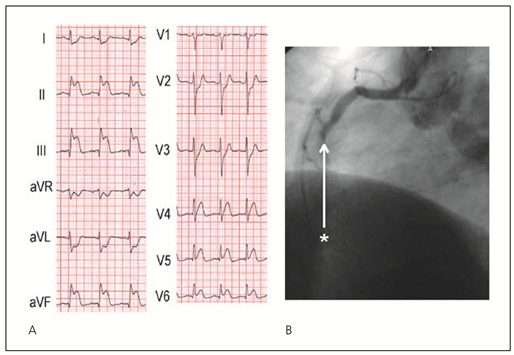

Das Vorhandensein von abnormalen Q-Zacken in Ableitungen mit ST-Hebungen im Eintritts EKG ist assoziiert mit einem grösseren Infarktareal und einer erhöhten Spitalmortalität [2]. Einige Patienten mit STEMI haben negative T-Wellen im EKG. Die T-Wellen-Inversion mit Verschwinden der ST-Hebung ist ein Zeichen der Reperfusion [12]. Patienten, die 2–6 Stunden nach Beginn der Symptomatik behandelt werden und T-Wellen-Inversionen in Ableitungen mit ST-Hebungen aufweisen, haben eine höhere Spitalmortalität als Patienten mit positiven T-Wellen. Dagegen haben Patienten mit negativen T-Wellen, die innerhalb 2 Stunden nach Beginn der Symptomatik behandelt werden keine erhöhte Spitalmortalität, dies im Gegensatz zu einer 5prozentigen Mortalitätsrate bei Patienten mit positiven T-Wellen [13]. ST-Hebungen mit negativen T-Wellen sind bei Patienten mit Beginn der Symptomatik vor mehr als 2 Stunden als Zeichen eines fortgeschritteneren Infarkt-Stadiums zu werten (Abb. 1 und 2).

Abbildung 1. 46jähriger Patient mit erstmaligen Thoraxschmerzen vor 2 Tagen bei anteroseptalem Myokardinfarkt. A. Im Eintritts-EKG zeigt sich eine fehlende R-Progression von V1–V4 und ST-Hebungen mit negativen T-Wellen in V2–V6. Diese Veränderungen sind als Zeichen eines fortgeschritteneren Infarkt-Stadiums zu werten. B. Das EKG nach interventioneller Eröffnung des RIVA zeigt eine Normalisierung der ST-Hebungen und der T-Negativierungen, die fehlende R-Progression über der Vorderwand persistiert. C. Koronarangiographisch zeigte sich ein Verschluss des Ramus interventricularis anterior nach Abgang des ersten Diagonalastes (Stern). Dg I = Ramus diagonalis I; RCX = Ramus circumflexus.